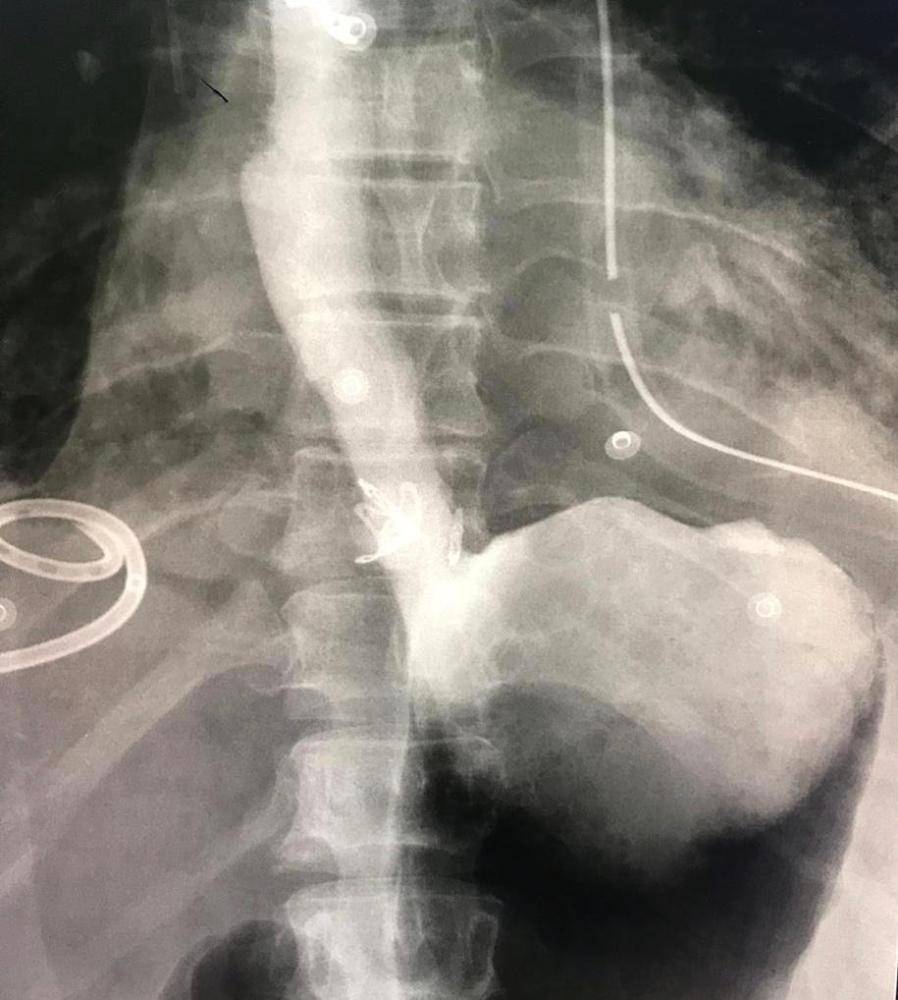

وقام الفريق الطبي بقيادة استشاري الدكتور عبدالناصر باطوق، واستشاري أمراض الجهاز الهضمي والكبد والمناظير التداخلية الدكتور محمد سعيد خان، بالتنسيق مع فريق التخدير وتحضير الحالة لغرفة العمليات، ووضعها تحت البنج الكامل، حيث تم التدخل بالمناظير غير الجراحية وتركيب دعامات المريء، وقفل الثقب باستخدام لاقطات المنظار الحديثة (OVESCO)، حيث تم التأكد من إقفال جميع طبقات جدار المريء ووضع دعامات معدنية، وكذلك بعمل الصبغة تحت الأشعة، إضافةً الى السيطرة على الالتهاب في التجويف الصدري بالتدخل الجراحي الصدري، حيث استمرت العملية ساعتين تكللت ولله الحمد بالنجاح.

وتم نقل الحالة إلى غرفة العناية المركزة وبعد ذلك إلى أقسام التنويم، حتى تماثلت الحالة للشفاء وتم خروجها وهي بأتم الصحة والعافية.